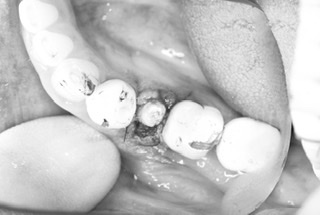

首都圏に不要不急の外出禁止要請が発令されてる中ですが、浅草橋の須田歯科クリニック分院では『食事をちゃんと取りたい』と希望される患者さんの右下5番の抜歯即時埋入のオペが朝からありました。

切開、抜歯から埋入、縫合までの全てを20分で終了。

その後は密着具合を示す値も良く、即日に仮歯まで装着してお帰り頂きました。